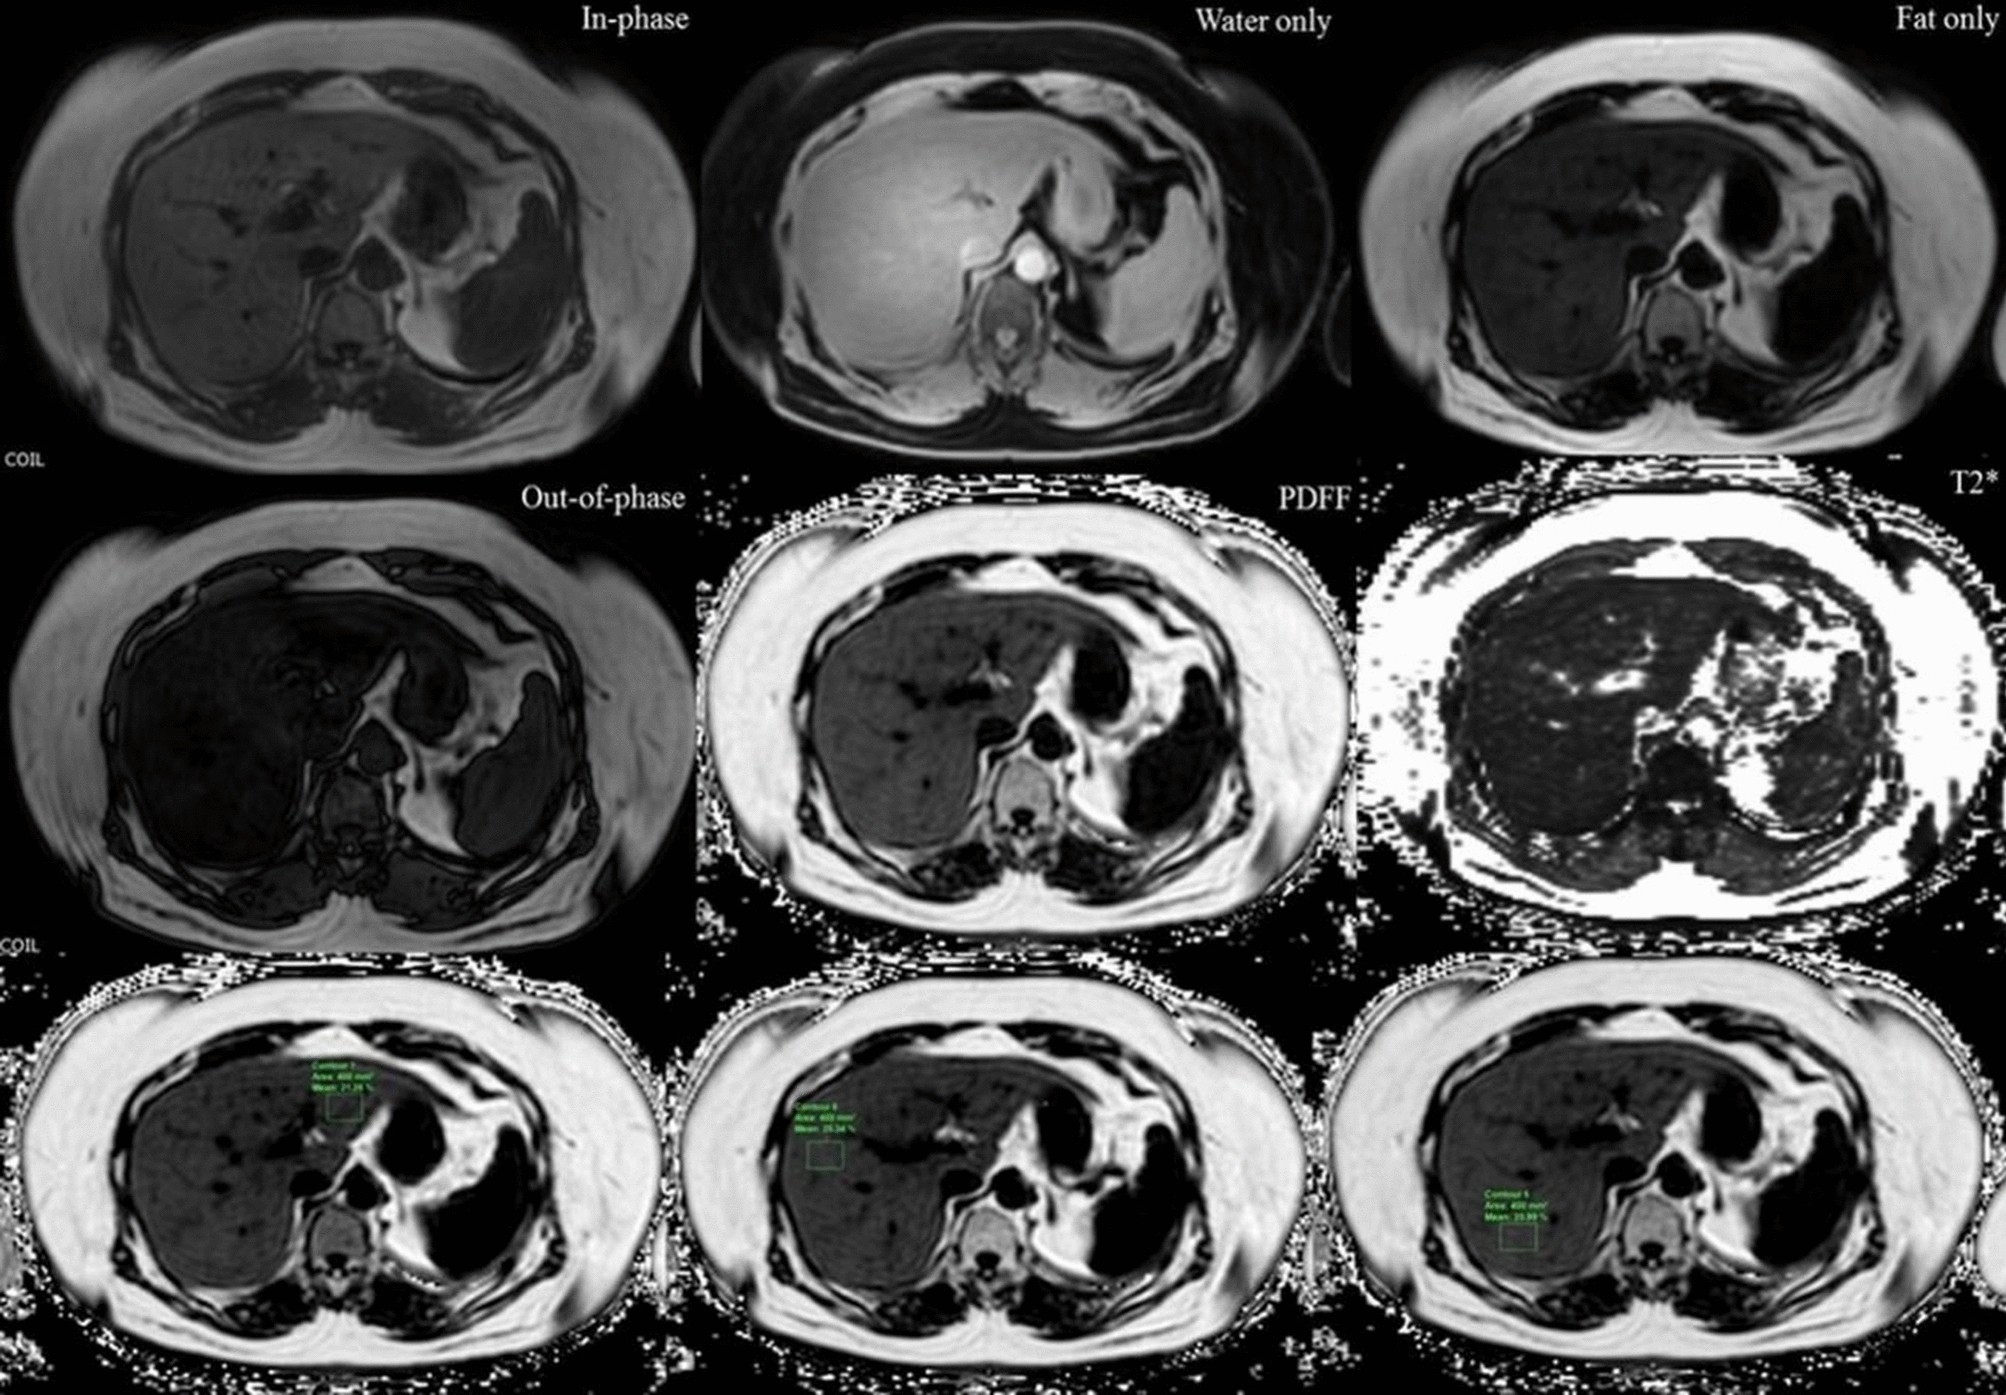

Figure 1

Moderate hepatic steatosis (40% steatosis on histologic analysis and 21.5% of PDFF) in a 63-year-old female on multi-echo DIXON image and PDFF map image. On the PDFF images (third row), mean percentage of PDFF of the left hepatic lobe 21.3%, anterior right hepatic lobe 25.3% and posterior right hepatic lobe 26%.